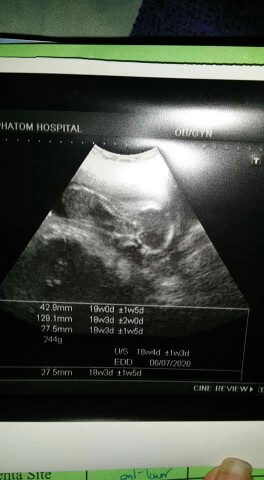

ตอน17+5ค่ะตอนนี้21+1